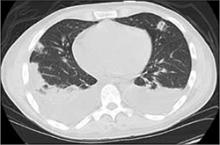

FIGURE 2

Chest CT shows pulmonary emboli

Our patient’s hospital course was complicated by the development of pulmonary septic emboli (FIGURE 2) and persistent fever. He underwent a successful tricuspid valve repair and was discharged with a peripheral IV to a skilled nursing facility to complete a 6-week course of IV cefazolin.